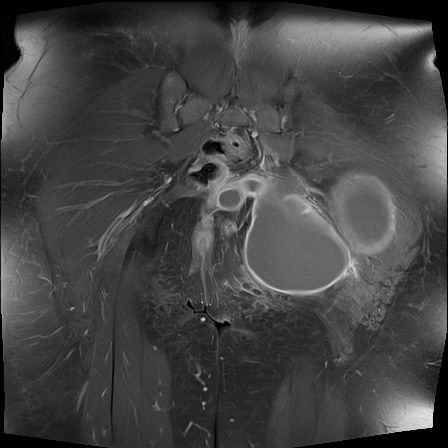

MRI

MRI chuỗi xung T1W sau tiêm thuốc tương phản từ của cùng bệnh nhân cho thấy bờ khớp cùng chậu không đều do bào mòn.

Có ngấm thuốc ở xương dưới sụn và phù nề tủy xương.

Không có tràn dịch khớp.

Thuốc tương phản từ tiêm tĩnh mạch không nhất thiết phải sử dụng để chẩn đoán viêm khớp cùng chậu.

Cuộn qua các hình ảnh MRI và so sánh với các dấu hiệu trên X-quang (hình ảnh cuối cùng).